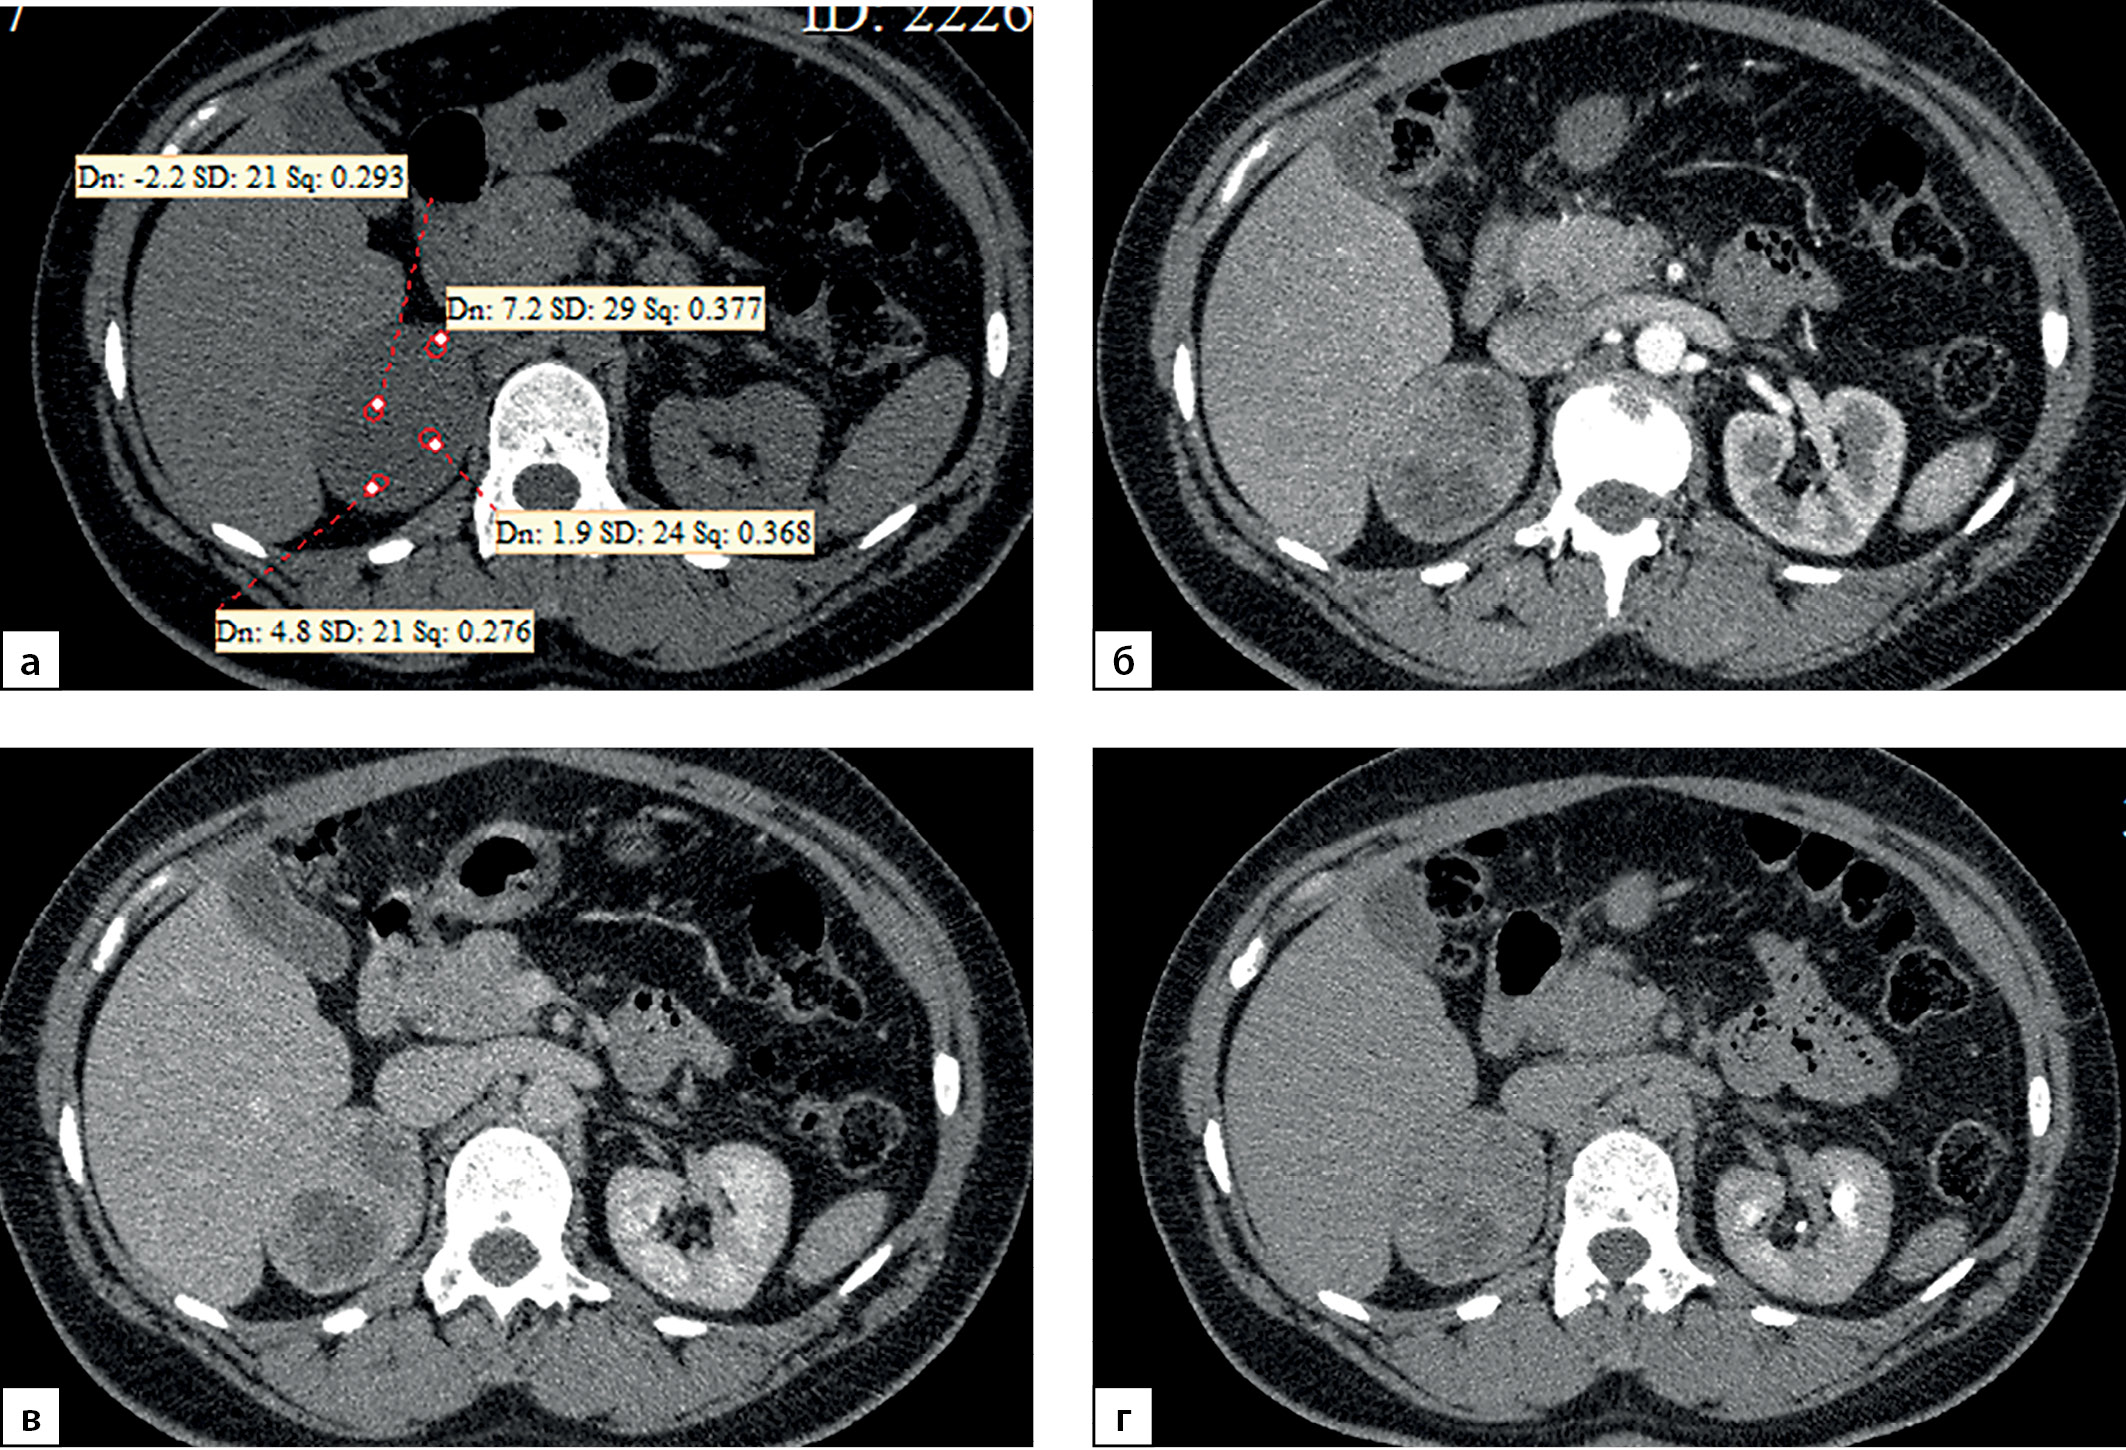

Медиана и интерквартильный размах максимальной нативной плотности АКР составили 32,0 (28,0–31,5) HU. Показатели нативной плотности в интервале от +10 до +30 HU отмечены у 22 больных (31,4%) пациентов, от +30 до +40 HU у 37 (52,9%) человек и свыше +40 HU в 10 (14,3%) наблюдений. Необходимо отметить, что в анализируемых наблюдениях встретился 1 пациент и с меньшей чем +10 HU нативной плотностью опухоли (рис. 9, 10). При выполнении денситометрии сознательно избегали попадания в зону измерения участков некроза, кистозных включений и кальцинатов.

Рисунок 9. Компьютерные томограммы пациентки С., 44 лет с крупной опухолью правого надпочечника размерами (66 мм): а — изображение в аксиальной плоскости, нативная фаза сканирования; образование имеет четкие ровными контуры, умеренно диффузно неоднородную структуру с низкими денситометрическими показателями от +2,2 до +7,2 HU; б — артериальная фаза постконтрастного сканирования; в — венозная фаза; г — фаза отсроченного сканирования. Коэффициент абсолютного вымывания контрастного препарата составил 42%, относительного — 38,1%.

Figure 9. Computed tomography of patient S., 44 years old, with a large tumor of the right adrenal gland (66 mm): a — image in the axial plane, native scanning phase; the formation has clear, even contours, a moderately diffusely heterogeneous structure with low densitometric values from +2.2 to +7.2 HU; b — arterial phase of post-contrast scanning; c — venous phase; d — delayed scan phase. The coefficient of absolute washout of the contrast agent was 42%, relative — 38.1%.

В 10% наблюдений (7 случаев) при КТ выявлены признаки инвазии опухоли в прилежащие анатомические структуры. Подобная ситуация встречается лишь у пациентов с опухолями большого размера. В 5 случаях при КТ определяется врастание опухоли в нижнюю полую вену (рис. 13), при этом в двух наблюдениях, кроме поражения вены (рис. 14), отмечена инвазия в ткань печени (1) и почки (1). В двух наблюдениях АКР распространялся на почку (1) и поджелудочную железу (1). В 8,6% наблюдениях (6 случаев) выявлялось увеличение забрюшинных лимфоузлов.

Рисунок 14. Компьютерные томограммы пациентки М., 41 года, с крупной опухолью правого надпочечника размерами до 90 мм: а — артериальная фаза постконтрастного сканирования, диффузно неравномерное накопление контрастного препарата, зона гиперперфузии в компримированном отделе правой доли печени; б — изображение, реформатированное в косой сагиттальной плоскости, венозная фаза сканирования; образование широко прилежит, деформирует нижнюю полую вену (стрелки). Во время операции потребовалось выполнение пластики нижней полой вены вследствие инвазии в последнюю опухоли надпочечника.

Figure 14. Computed tomography of patient M., 41 years old, with a large tumor of the right adrenal gland up to 90 mm in size: a — arterial phase of post-contrast scanning, diffusely uneven accumulation of the contrast agent, hyperperfusion zone in the compressed section of the right lobe of the liver; b — image reformatted in the oblique sagittal plane, venous phase of the scan; the mass is widely adjacent, deforming the inferior vena cava (arrows). During the operation, plastic surgery of the inferior vena cava was required due to invasion into the last tumor of the adrenal gland.